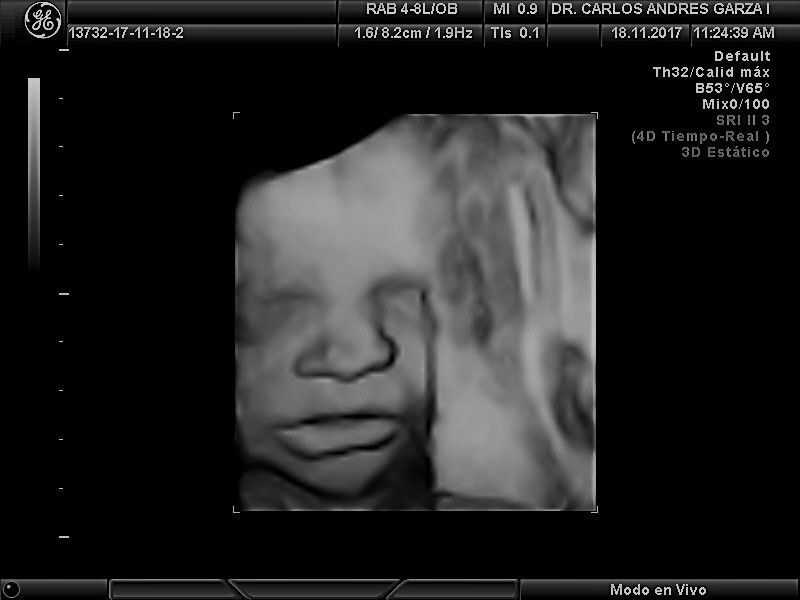

Ultrasonido 4D

!Conoce a tu bebé hoy¡ Se trata de la última tecnología en ecografía o ultrasonido a nivel mundial, que consiste en un procesamiento de reconstrucción digital de imágenes para formar una sola imagen en 4 dimensiones, permitiendo así poder visualizar cualquier estructura tal cual la estuviésemos viendo directamente el rostro de tu bebé, antes de nacer. Con esta nueva generación de tecnología del ultrasonido puedes observar datos mas detallados de su bebé, sus movimientos, gestos, risas, bostezo, etc... tal como si lo tuviera en sus brazos. En el pasado los papas no conocían la cara de su bebe hasta que naciera.